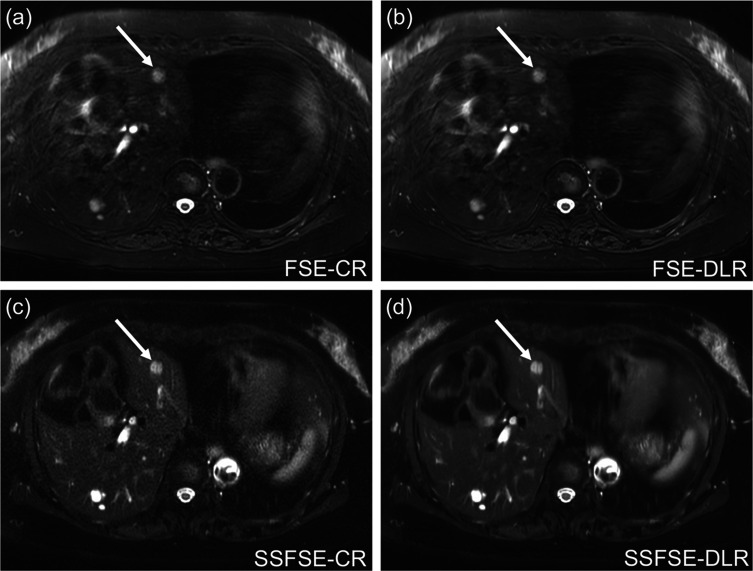

Methods: Respiratory-triggered fat-suppressed liver T2-weighted MRI was obtained with the FSE and SSFSE sequences at the same spatial resolution in 55 patients. Conventional reconstruction (CR) and DLR were applied to each sequence, and the SNR and liver-to-lesion contrast were measured on FSE-CR, FSE-DLR, SSFSE-CR, and SSFSE-DLR images. Image quality was independently assessed by three radiologists. The results of the qualitative and quantitative analyses were compared among the four types of images using repeated-measures analysis of variance or Friedman's test for normally and non-normally distributed data, respectively, and a visual grading characteristics (VGC) analysis was performed to evaluate the image quality improvement by DLR on the FSE and SSFSE sequences.

Results: The liver SNR was lowest on SSFSE-CR and highest on FSE-DLR and SSFSE-DLR (P < 0.01). The liver-to-lesion contrast did not differ significantly among the four types of images. Qualitatively, noise scores were worst on SSFSE-CR but best on SSFSE-DLR because DLR significantly reduced noise (P < 0.01). In contrast, artifact scores were worst both on FSE-CR and FSE-DLR (P < 0.01) because DLR did not reduce the artifacts. Lesion conspicuity was significantly improved by DLR compared with CR in the SSFSE (P < 0.01) but not in FSE sequences for all readers. Overall image quality was significantly improved by DLR compared with CR for all readers in the SSFSE (P < 0.01) but only one reader in the FSE (P < 0.01). The mean area under the VGC curve values for the FSE-DLR and SSFSE-DLR sequences were 0.65 and 0.94, respectively.

Conclusion: In liver T2-weighted MRI, DLR produced more marked improvements in image quality in SSFSE than in FSE.